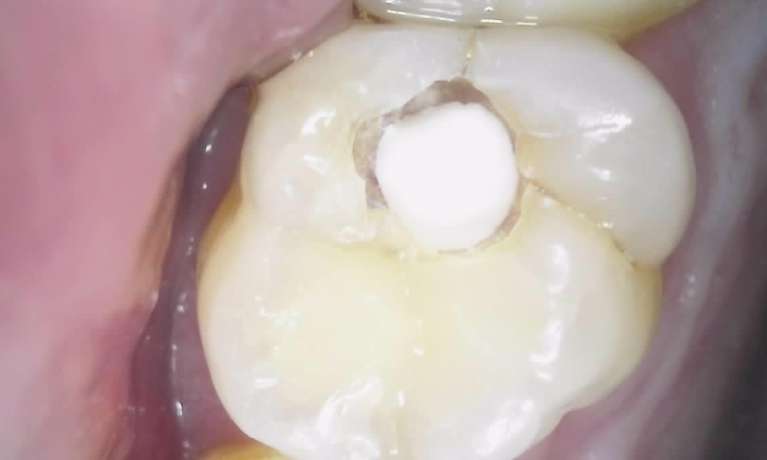

We take great pride in the services we perform in our office. We always try to not only meet your expectations, but we also try to exceed them. There are many types of services that we perform in our office, as well as others that we perform in coordination with highly skilled specialists. We have compiled a few examples of the treatments that we have performed. We are proud to say that these are the usual results our patients expect to see.

The photos are not retouched, nor are they taken by a professional photographer. These are just the routine treatment photos that we take and the results that we see every day. They are by no means a comprehensive catalog of the procedures that we perform. They are just a small sample of some of the results you can expect when you seek treatment in our office.